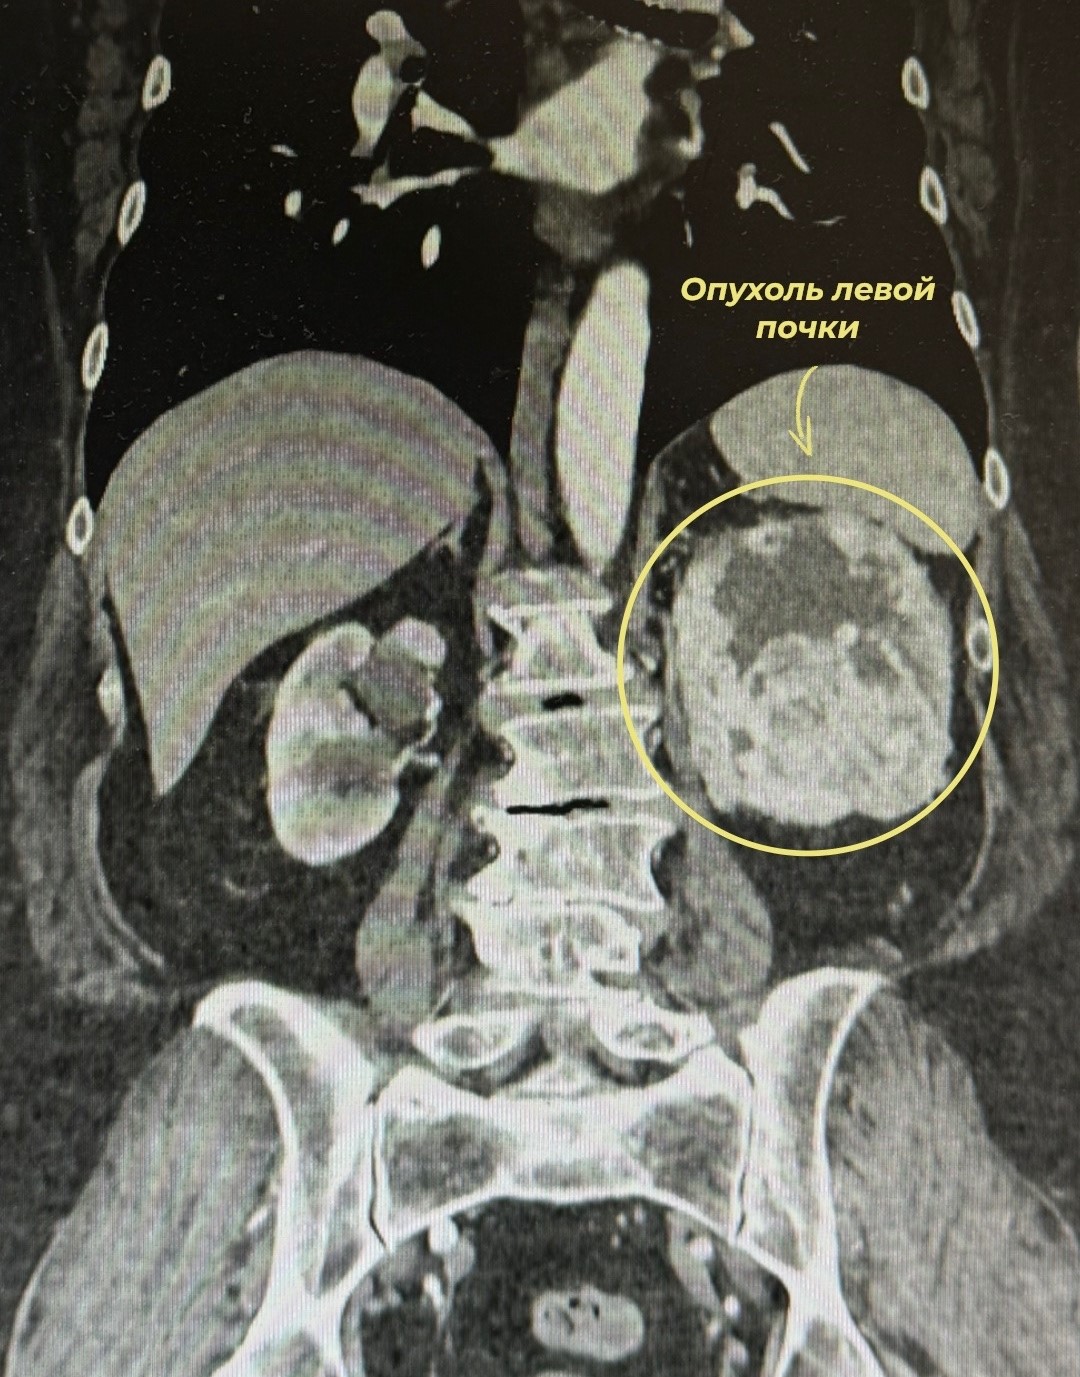

С самого начала рак никак себя не проявлял – женщина пришла к врачам уже когда появились тянущие боли в пояснице и кровь в моче. На МСКТ врачи обнаружили злокачественное новообразование левой почки, оцененное по системе R.E.N.A.L. в 10 баллов.

"Врачами урологического отделения диспансера выполнена радикальная лапароскопическая нефрэктомия слева. Операция прошла успешно, несмотря на ее сложность", − говорится в сообщении.